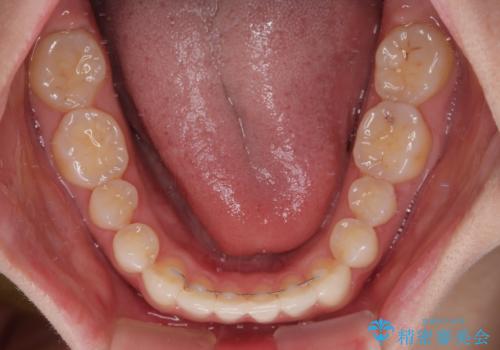

上下前歯同士の距離が離れているため、上顎左右第一小臼歯2本を抜歯することで前突を改善することとしました。

しかしながら、左右ともに側切歯が矮小歯であるため、矯正治療で矮小歯前後にスペースを作り、矯正治療後にオールセラミッククラウンにて補綴治療を行うこととしました。

治療途中で地元へ転居され、飛行機での通院となったため、治療期間が長くなりましたが、自然で整った口元に仕上げることができました。